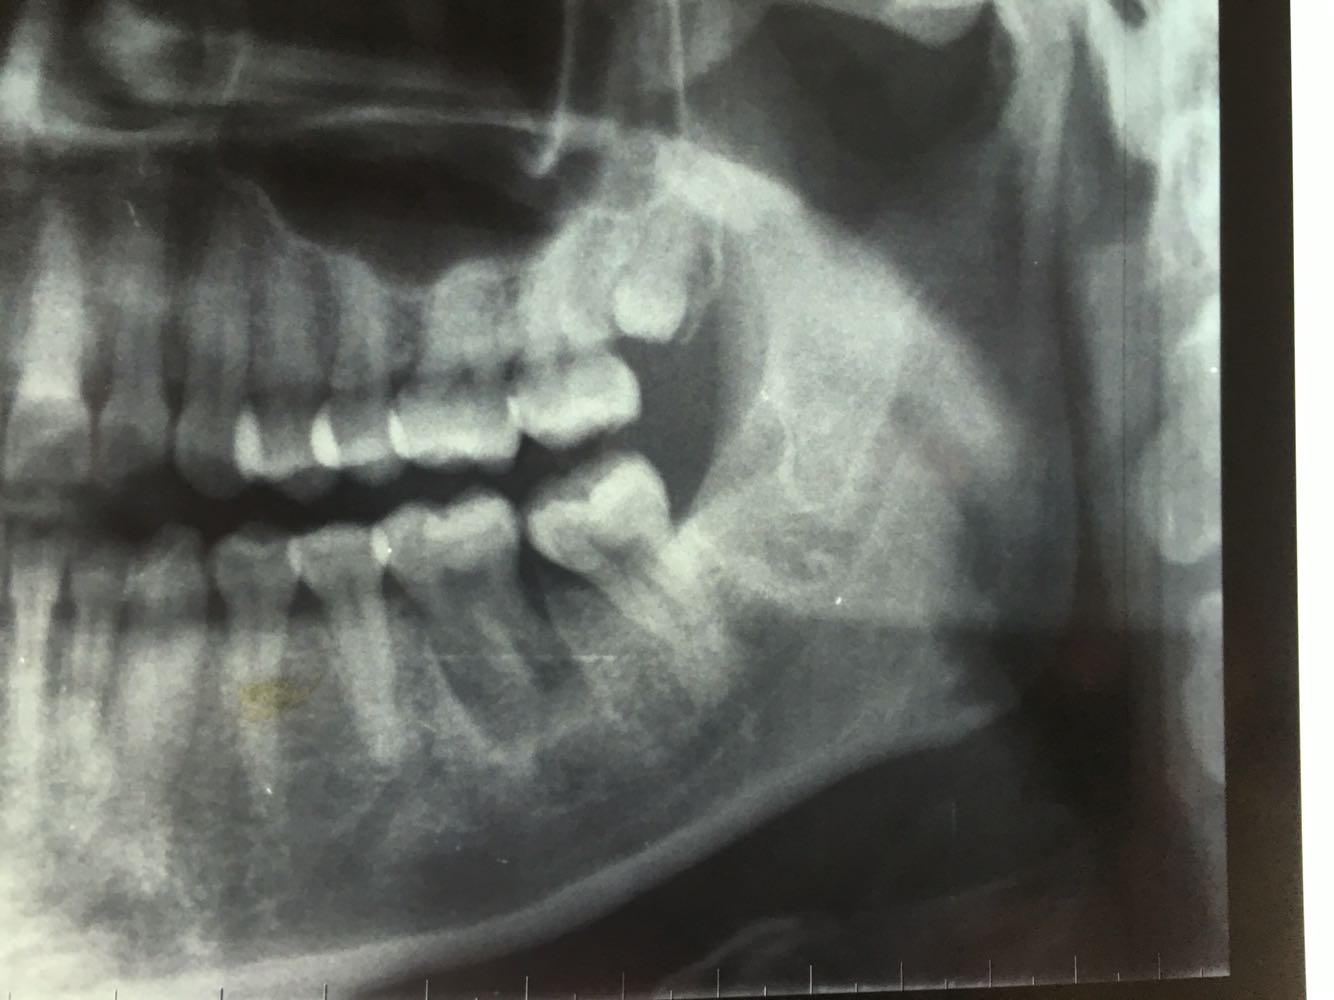

主诉:左下后牙反复肿痛

左下6残根,8正位,对颌未萌出,

讨论:患者本来是要求拔除左下6残根的,进修医生拔除残根后本人建议自体牙移植,患者接受了我的经验,把8拔除后移植到6的位置,目前还在随访中